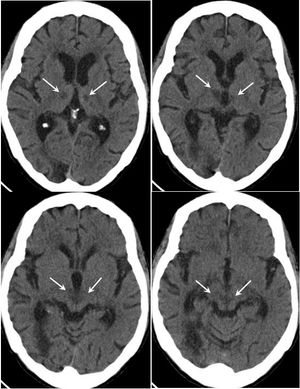

Here, view results of CT of the head and axial FLAIR and axial diffusion-weighted MRI studies. What is in your differential? What is your diagnosis?